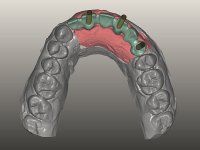

O paciente foi observado conjuntamente e a dúvida que surgiu de imediato foi se seria possível com a regeneração óssea a efectuar poder ser reabilitada naturalmente a zona das papilas interdentárias. Nesse sentido foi feito um enceramento de diagnóstico que contemplaria as duas hipóteses, utilizando ou não a cerâmica gengival. A confecção desse enceramento foi fundamental para expor ao paciente a dificuldade da reabilitação. O wax-up deu origem a um mock-up que foi aprovado pelo paciente e que simultaneamente serviu de guia imagiológica. O caso foi planificado cirurgicamente e realizada uma guia cirúrgica com que foram colocados os implantes. Após 10 semanas foi feita a 1ª impressão para confecção da ponte provisória. Foram criados os primeiros perfis de emergência na gengiva artificial e foi digitalizado o modelo. Por processo de CAD-CAM foi confeccionada uma ponte provisória aparafusada baseada no enceramento de diagnóstico. A ponte trabalhou durante 8 semanas os tecidos moles que foram fielmente copiados numa impressão com técnica de moldeira aberta. Os transferes foram individualizados com resina composta para copiarem fielmente os perfis de emergência criados pela ponte provisória. Confeccionado o modelo de trabalho definitivo, foi realizada uma infra-estrutura em zircónio seguindo a orientação do enceramento de diagnóstico. O assentamento da infra-estrutura foi testado em boca e simultaneamente foi novamente impressionados os tecidos moles com um silicone fluido. Nessa consulta foi feito o levantamento da cor. Os dentes 13 e 23 apresentavam uma saturação anormalmente forte que resolvemos não valorizar, optando por privilegiar a relação com o sector antero-inferior. Foi realizada uma nova gengiva artificial com a impressão que acompanhou a impressão de arrasto com a infra-estrutura. Após a colocação da cerâmica na infra-estrutura foram coladas as meso-estruturas. O trabalho final foi aparafusado lentamente permitindo a adaptação dos tecidos moles.